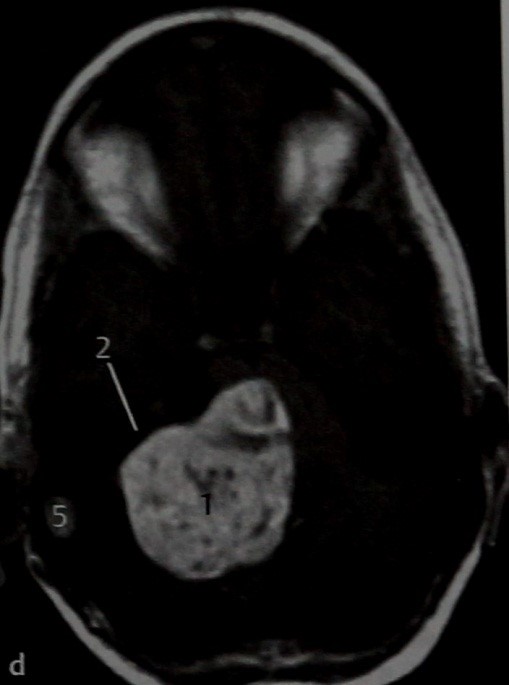

МРТ: Т2-взвешенное изображение в горизонтальной проекции. Опухоль имеет средние размеры (1), расположена в области мостомозжечкового угла и отчасти во внутреннем слуховом проходе и касается ствола мозга (2). Хотя нет четких признаков, указывающих на то, что латеральная часть внутреннего слухового прохода, т.е. его дно, заполнена жидкостью, какое-то количество ее все же имеется (З), сама опухоль не выходит за пределы медиальной части внутреннего слухового прохода.

Пациент, обратившийся по поводу подостро развившейся односторонней тугоухости. МРТ:Т1-взвешенное изображение в горизонтальной проекции после введения препарата гадолиния. На данной МРТ представлен случай более крупной шванномы преддверно-улиткового нерва. Опухоль накапливает КС, заполняет внутренний слуховой проход, и значительная часть ее достигает мостомозжечкового угла (1). Учитывая отчетливое контрастное усиление и характерную локализацию опухоли, можно предположить с большой долей вероятности, что это шваннома преддверно-улиткового нерва. Участки опухоли, которые не накапливают КС (2), по-видимому, соответствуют кистозному перерождению, часто наблюдаемому при шванномах. Видно, что опухоль сдавливает ствол мозга (3) и мозжечок (4). Отмечается слабо выраженная реакция твердой мозговой оболочки, которая более характерна для менингиомы. Кзади от опухоли, возможно, имеется арахноидальная киста (5), которая иногда образуется из-за скопления ЦСЖ, связанного с вызываемым опухолью масс-эффектом.

МРТ: Т1- (b) и Т2-взвешенное (с) изображения и Т1-взвешенное изображение с контрастным усилением (d) в горизонтальной проекции. Гигантская опухоль, локализующаяся в области мостомозжечкового угла (Т); отмечаются гипоинтенсивный сигнал на Т1 -взвешенном изображении и гиперинтенсивный - на Т2-взвешенном изображении и усиление сигнала после введения КС. Контрастного усиления внутреннего слухового прохода (2) не происходит. Хотя такая картина для шванномы менее типична, исключить эту опухоль нельзя, учитывая ее округлую форму и ряд других особенностей. Отмечается выраженная компрессия ствола мозга (3) и мозжечка (4). Контрастное усиление содержимого сигмовидного синуса (5) в сочетании с гиперинтенсивным сигналом на Т1 -взвешенном изображении указывает на тромбоз синуса.